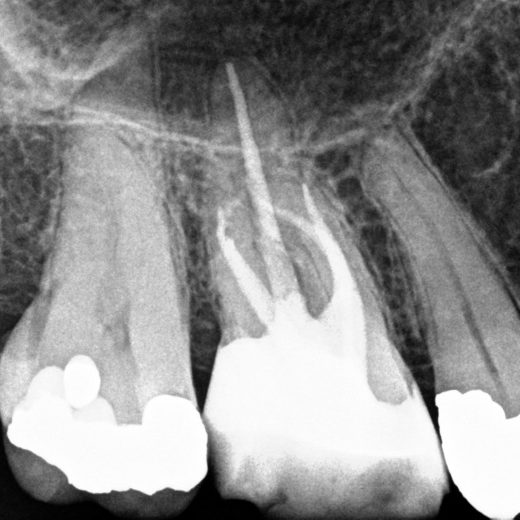

Figure 11: Complex MB1/MB2 anatomy (2-1-2 morphology)

- Preoperative radiograph

- A paper point has been placed in MB2, and can be seen appearing in MB1 where the canals join

- Mid-fill radiograph showing the MB2 has a separate apical foramen from MB1. The MB1 and MB2 have a 2-1-2 morphology (two orifices-merging into one canal – separating into two canals). The MB2 should always be fully instrumented because this anatomy is difficult to predict

- Postoperative radiograph

- Microscope photograph.